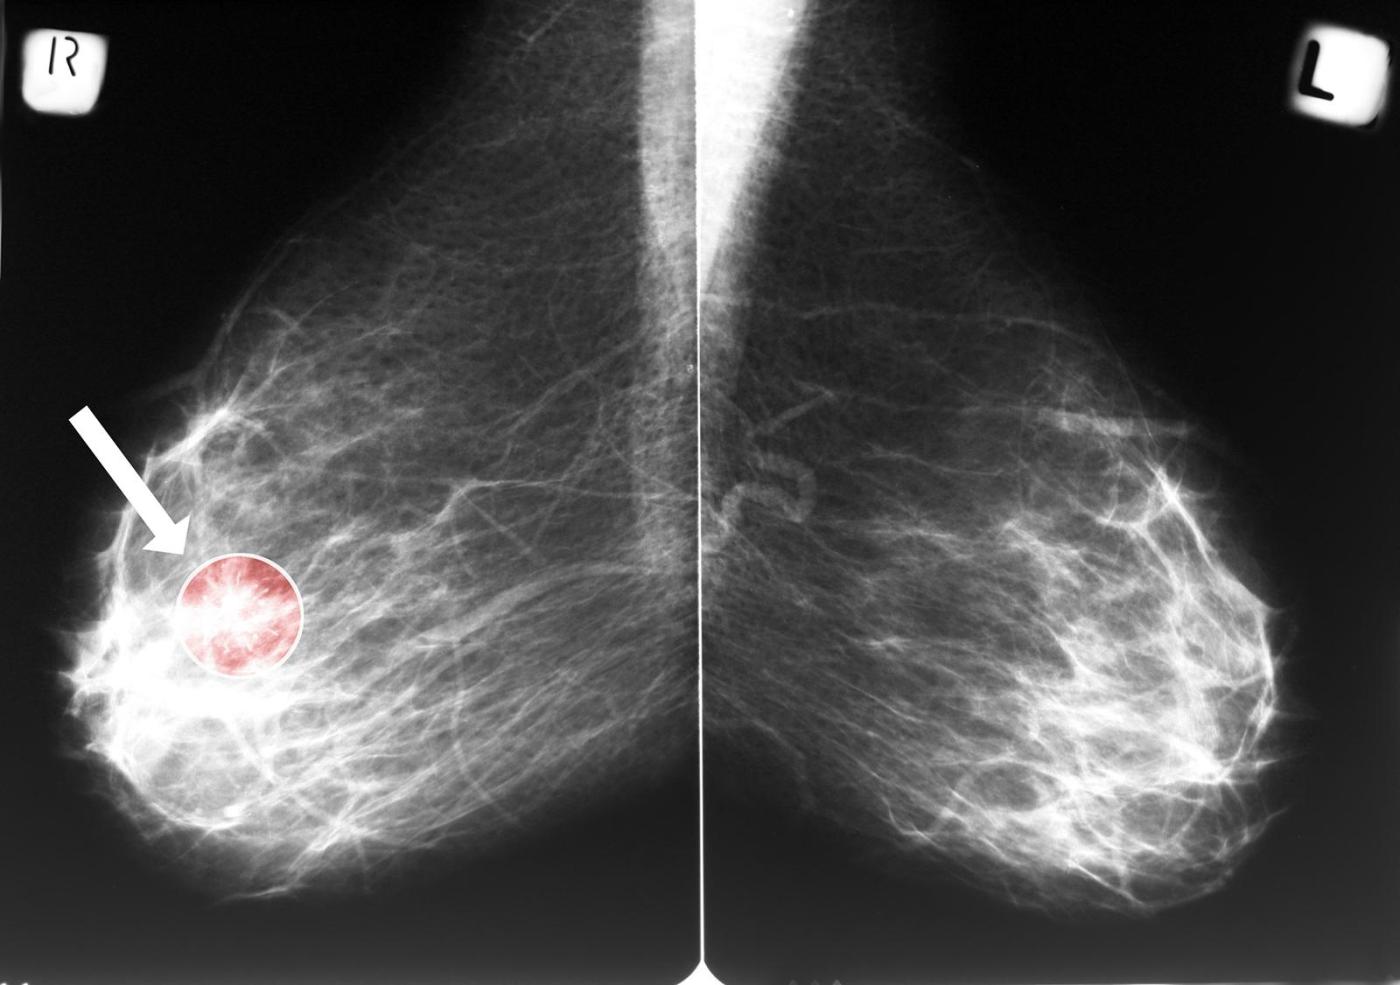

A study presented at a Dec. 3 Radiological Society of North America meeting found that calcium deposits visible in the arteries of the breast can help predict a woman’s future risk of heart attack, heart failure, stroke and death. The findings add to growing evidence that mammograms may hold untapped value beyond cancer screening.

The condition that mammograms can detect — and act as an early warning of heart problems down the road — is called breast arterial calcification, said Matthew Nudy, an assistant professor of medicine and public health sciences at Penn State College of Medicine who presented the findings.

Breast arterial calcification, or BAC, is relatively common, appearing in an estimated 15% to 25% of screening mammograms. Yet it is not routinely reported.

Despite often being discernible on routine mammograms, radiologists do not typically report the presence of these calcifications “because there’s no known association between this breast arterial calcification and breast cancer,” Nudy said.